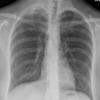

Lymphoma PA (DLBC)

Date: 04/25/2009

Views: 3515